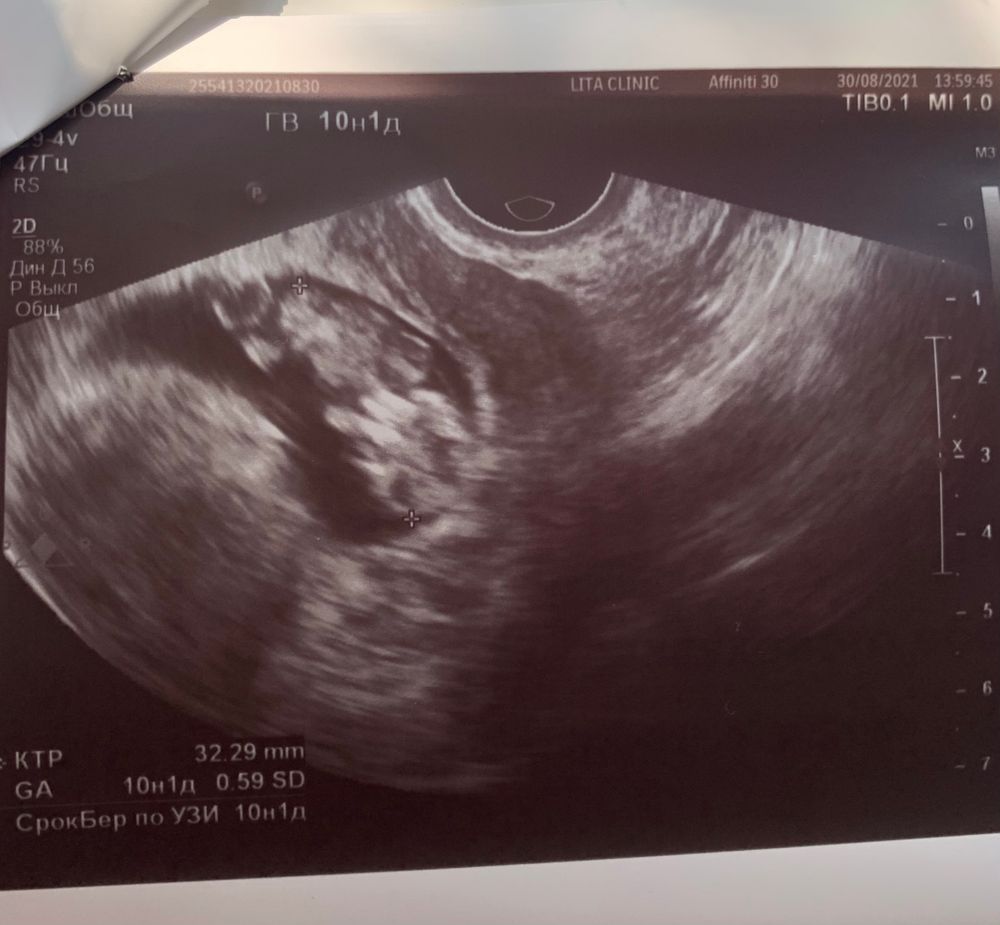

10 недель УЗИ. Мысли о скрининге и нипт.

Добра мира и любви, потому что его максимальный размер в источниках - 6 мм... тем более с 8 10 неделю он должен уменьшаться, а у меня наоборот вырос.. а к 12 недели исчезнуть